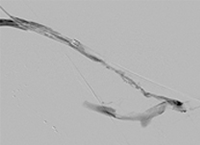

Collection bag after treatment.

Collection bag after first pass

Clot from single pass of distal iliac and common femoral